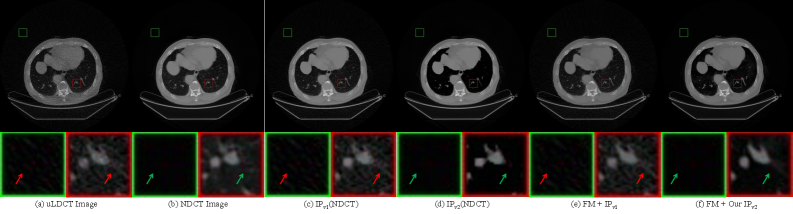

Figure 1(a) shows an ultra-low-dose CT image with severe noise contamination. Figure 1(b) presents the corresponding normal-dose CT image. A comparison of the red enlarged regions in Figure 1(a) and (b) reveals evident discrepancies in anatomical morphology. Training a network directly on such unaligned image pairs causes the model to learn incorrect mapping relationships, which leads to anatomical distortion in the denoised results. In particular, the original tissue structures in the input uLDCT image cannot be faithfully preserved, and such structural inconsistency directly undermines diagnostic accuracy.

Figure 1(c) illustrates the NDCT processed by the original image purification strategy, which serves as the evaluation label for denoising networks, while Figure 1(d) shows the NDCT processed by the improved purification strategy. A comparison between these two labels indicates that, in the background and lung tissue regions, the label generated by IPv2 contains substantially less residual noise than that produced by IPv1.

Figure 1(e) and (f) further compare the denoising performance before and after the proposed improvement. Figure 1(e) presents the result obtained by training a FM[18] model in an end-to-end manner on the data shown in Figure 1(a). The red arrows indicate that the model fails to suppress noise in the background and lung tissue regions. In contrast, Figure 1(f) shows the denoised output of the FM[18] model trained under the IPv2 strategy. The green arrows demonstrate that, while maintaining the denoising capability of IPv1 in the chest wall and skeletal regions, IPv2 further enhances noise suppression in the background and lung tissue regions.

Refer to caption

Figure 1: Motivation of the improved image purification strategy (IPv2). (a) Ultra-low-dose CT (uLDCT) image with severe noise that degrades structural clarity. (b) Corresponding normal-dose CT (NDCT) image. (c) NDCT processed by the IPv1 strategy, which serves as the test label. (d) NDCT processed by the IPv2 strategy. (e) Denoising result of (a) obtained by training a flow matching[18] (FM) model in an end-to-end manner under the IPv1 strategy. (f) Denoising result of (a) obtained by training a FM[18] model in an end-to-end manner under the IPv2 strategy. The green enlarged boxes in (a) to (f) indicate background regions, and the red enlarged boxes indicate lung tissue regions. The red arrows denote the presence of noise, while the green arrows denote the absence of noise. Please zoom in for details.